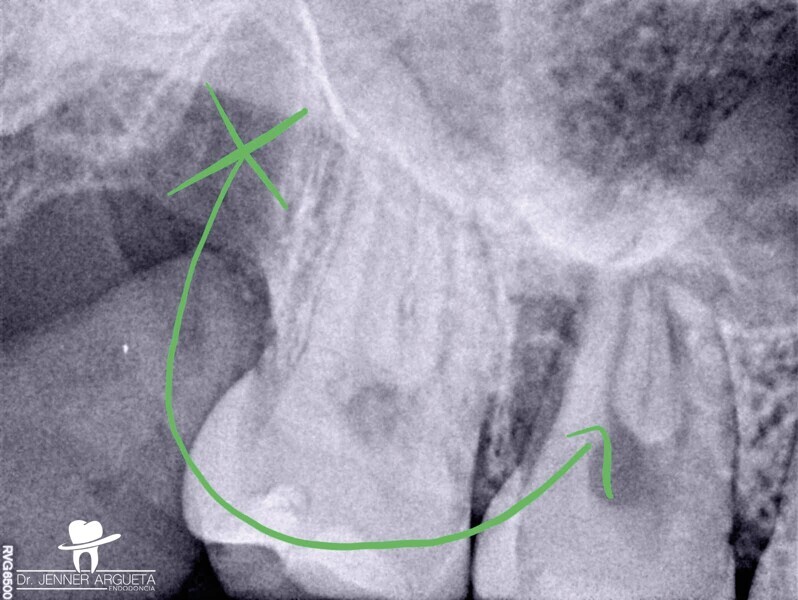

La patiente s’est présentée au cabinet huit mois plus tard avec des signes et des symptômes de nécrose pulpaire et d’abcès périapical aigu mis en évidence par une radioclarté. La zone rétromolaire était bien cicatrisée (Fig. 6). Dans des cas comme celui-ci, où la structure coronaire est encore intacte, il est conseillé de recourir aux nouvelles techniques endodontiques et d’adopter une approche conservatrice du traitement endocanalaire afin d’obtenir de meilleurs résultats. Le puits d’accès endodontique a été créé au moyen de fraises à haute vitesse et d’inserts ultrasoniques. Le protocole de nettoyage et de mise en forme a été réalisé à l’aide de canules et de limes flexibles en alliage à mémoire de forme contrôlée (Aurum Blue, Meta Biomed), dont les propriétés sont particulièrement importantes lors de la pénétration dans les canaux radiculaires par l’accès conservateur (Figs. 7a et b).

Les limes endodontiques dont l’alliage est stabilisé en phase martensitique (mémoire de forme contrôlée) sont en effet dotées d’une meilleure résistance à la fatigue cyclique.11, 13, 14 Les canaux radiculaires ont été obturés au moyen d’un ciment de scellement endodontique à base de silicate de calcium activé par ultrasons (CeraSeal et EQ-S, Meta Biomed) et de gutta-percha (Figs. 8a–c). Cette étape du traitement peut s’avérer délicate en présence d’un accès endodontique de très petite taille.

L’utilisation d’un ciment de scellement endodontique à base de silicate de calcium facilite le processus d’obturation, et l’activation ultrasonique permet de distribuer le matériau sur toute la longueur du système des canaux radiculaires nettoyés et mis en forme (Fig. 9). Une restauration coronaire adhésive a été effectuée dans le cadre de la même visite au moyen d’un matériau de reconstitution corono-radiculaire à double polymérisation (NexCore, Meta Biomed) pour la cavité pulpaire et d’un composite compactable pour la surface occlusale (Ezfi l, Meta Biomed ; Figs. 10a et b). La dent était fonctionnelle et asymptomatique, et la patiente a dès lors pu commencer son traitement orthodontique. La radiographie prise à l’occasion du suivi à trois ans a montré un tissu périapical sain (Fig. 11).

Lorsqu’un traitement endocanalaire de la dent transplantée est nécessaire, il est conseillé de planifier l’intervention en fonction de l’état des structures coronaires et radiculaires. La préservation du tissu dentaire doit être l’un des objectifs principaux, notamment pour obtenir une dent dont la résistance sera minimalement affectée par les charges occlusales et les sollicitations fonctionnelles. L’un des plus grands risques lors de la réalisation d’un traitement endocanalaire conservateur est la contrainte en flexion accrue sur les limes au moment du passage au travers des puits d’accès de petite taille ; les contraintes en flexion sont plus élevées à l’entrée du canal radiculaire en raison de l’absence d’accès rectiligne. La fatigue cyclique peut également augmenter au niveau des courbures et mener à un transport plus important du canal radiculaire, ainsi qu’à une modification de son anatomie initiale. Si la fatigue cyclique représente l’un des risques majeurs liés aux puits d’accès endodontique, il est conseillé d’utiliser des limes ayant une résistance accrue aux contraintes ou déformations répétées.18